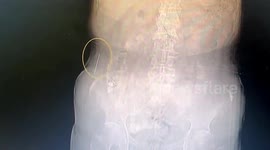

POWER ACCUPUNCTURE WITH LONGEST NEEDLES

I returned to Dr. Shu Jun's Chinese Medicine clinic to try Power Accupuncture with the longest needles going, moxibustion and her new Tai Chi Ball. Would I find a need for needles or just be punctured?